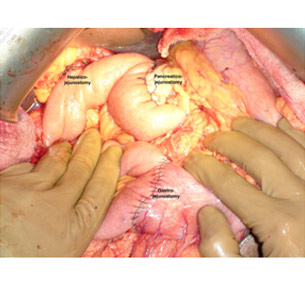

Reconstruction is done by a Pancreatico-jejunostomy preferably a duct to mucosa, biliary enteric & a gastro-jejunostomy for continuity. Our large experience & increasing numbers have led to lowering of the mortality (5%) over the years. The pancreatic leak rate has also reduced to around 12%. Five year survivals vary from 15% to 50% depending on the type of pathology.

Intra operative photo after radical resection

Intraoperative photo showing all the anastomosis